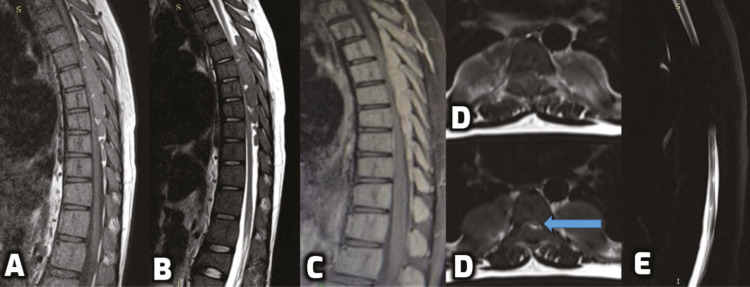

Case description: This report describes a young male with thalassemia major, who presented with symptomatic cord compression due to a thoracic intraspinal lesion. It was surgically excised and diagnosed as a case of EMH. The boy recovered fully and has been asymptomatic for six months now.

Conclusion: The occurrence of EMH in the thoracic spine is uncommon, whereas symptomatic cord compression as a result of it is even more unusual. Magnetic resonance imaging (MRI) is the diagnostic imaging of choice and treatment options that can be offered are surgical decompression, radiotherapy, hydroxyurea, and transfusion of packed red blood cells (RBCs).